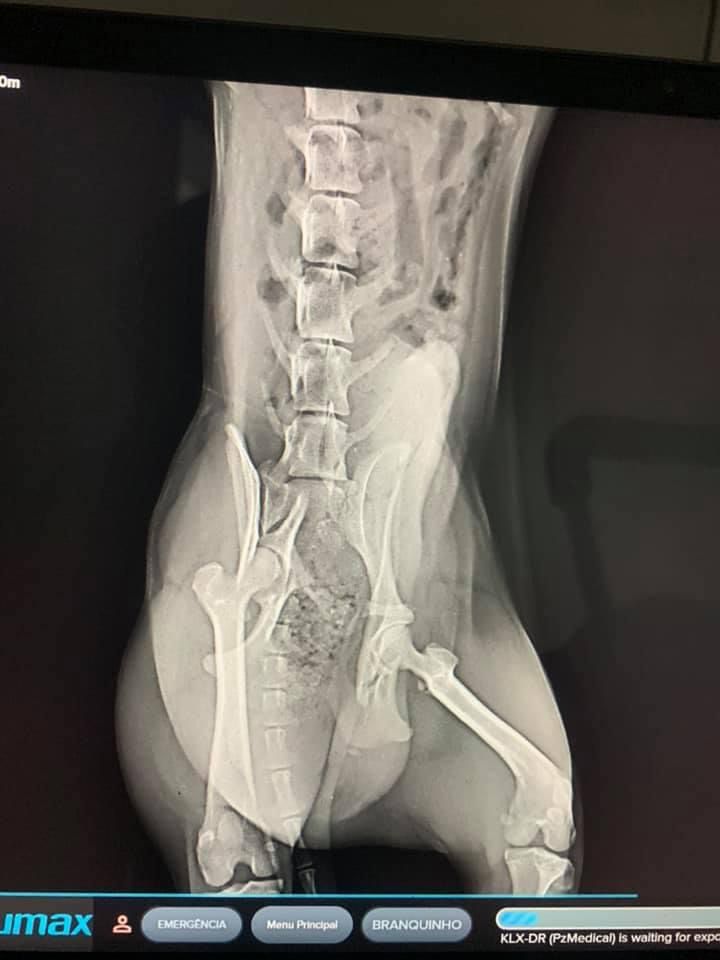

E o resultado dos exames realizados não trouxeram boas notícias. “Um amigo nosso Luciano Flores, pagou a radiografia e nela foram confirmadas duas fraturas: no fêmur e na pelve e é cirúrgico”, conta Day.

Confira as imagens do exame de Branquinho: